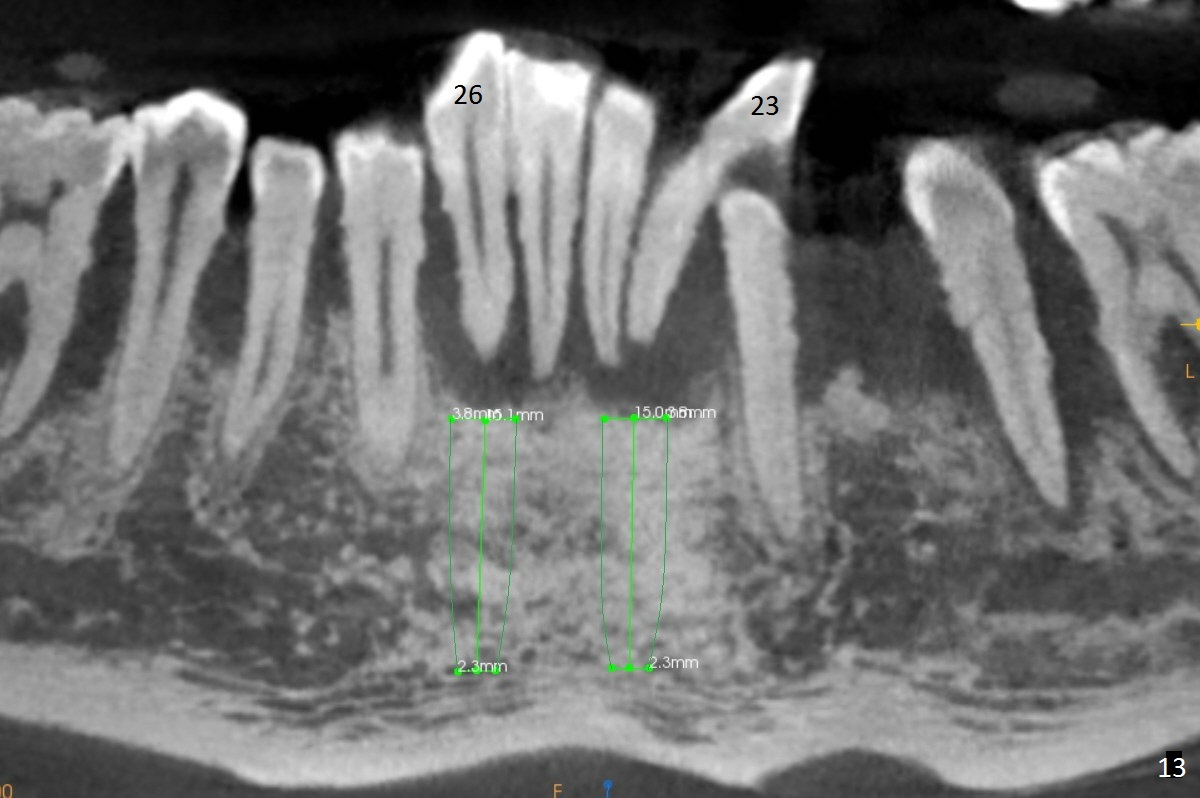

Class II Division II malocclusion (Fig.2,6) will make it difficult to restore #23-26 implant-supported FPD. Although the teeth #7-10 may need to be replaced later (Fig.7,8), enameloplasty will be conducted for #7-10 (Fig.9 white area; Fig.12 black circles (gross reduction)) prior to #23-26 extraction and implant placement (Fig.10). To be flexible in restoration (angulation) and possible future hybrid denture, 2-piece narrow implants will be placed (3.0 or 3.3 mm) instead of 1-piece ones. In fact CBCT shows that the narrowest regular implant (3.8 mm) can be placed in the lower anterior region (Fig.13-15).